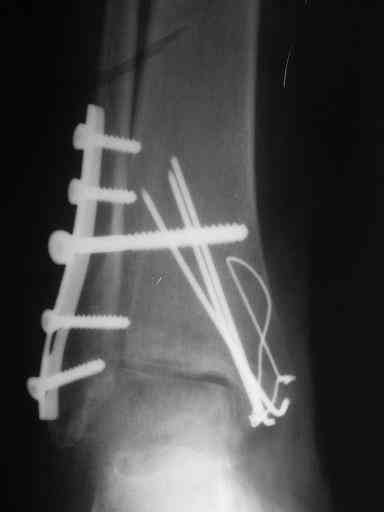

Завершая презентацию случая хотим показать результат операции. Прооперировали больную в соседнем отделении. На операции выраженый рубцовый процес в области синдесмоза, остеопоротические изменения в области медиальной и латеральной лодыжек. Провели удаление рубцовой ткани, остеосинтез медиальной и латеральной лодыжек с позиционным винтом на синдесмоз.Фото прилагаем. Благодарим за отзывы.